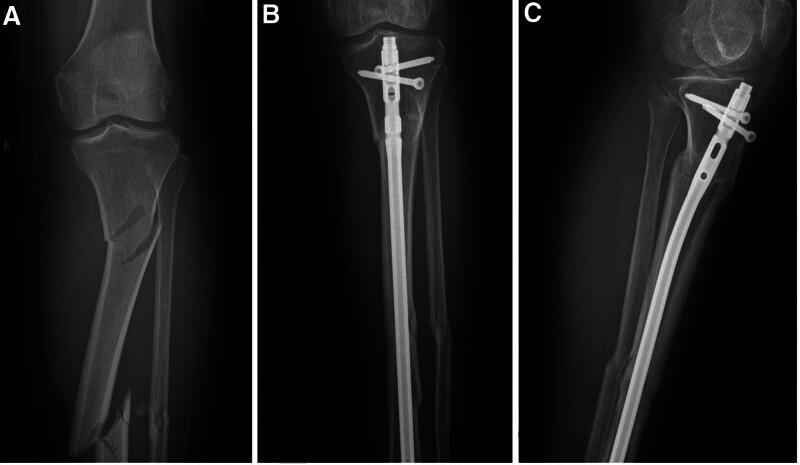

It is unclear whether small plates are needed for augment fixation to provide a more stable mechanical environment in segmental fractures of the tibia treated with intramedullary nail. The purpose of this study was to investigate the efficacy of intramedullary nailing combined with locking plates in the treatment of segmental fractures of the tibia. This study included 41 patients with segmental tibia fractures between January 1, 2018 and January 1, 2023. Eighteen patients were treated with an intramedullary nail assisted by a locking plate (combination group), and 23 patients were treated with an intramedullary nail without a plate (nail group). The perioperative parameters of all patients were recorded, and clinical efficacy was evaluated during follow-up. The operation time was shorter but the incision was longer in the combination group (P < .05). The numbers of fluoroscopy procedures and the time to union were shorter in the combination group (P < .05). The rate of malunion in the nail group (4, 17.4%) was significantly greater than that in the combination group (0, 0%). At the last follow-up, no statistically significant differences in walking ability were detected. Our results suggest that a locking plate combined with an intramedullary nail for segmental tibial fractures may require a longer surgical incision, but it has significant advantages such as a shorter operative time and time to union, a shorter fluoroscopy time, and a lower rate of malunion and nonunion. Intramedullary nail fixation assisted by a locking plate is an effective method for treating segmental fractures of the tibia.

对于在使用髓内钉治疗的胫骨节段性骨折中,是否需要小钢板进行增强固定以提供更稳定的力学环境尚不清楚。本研究的目的是探讨髓内钉联合锁定钢板治疗胫骨节段性骨折的疗效。本研究纳入了2018年1月1日至2023年1月1日期间的41例胫骨节段性骨折患者。18例患者采用锁定钢板辅助髓内钉治疗(联合组),23例患者采用无钢板髓内钉治疗(髓内钉组)。记录所有患者的围手术期参数,并在随访期间评估临床疗效。联合组手术时间较短但切口较长(P < 0.05)。联合组的透视次数和骨折愈合时间较短(P < 0.05)。髓内钉组的畸形愈合率(4例,17.4%)显著高于联合组(0例,0%)。在最后一次随访时,未检测到步行能力的统计学显著差异。我们的结果表明,锁定钢板联合髓内钉治疗胫骨节段性骨折可能需要更长的手术切口,但具有手术时间和骨折愈合时间短、透视时间短以及畸形愈合和不愈合率低等显著优势。锁定钢板辅助髓内钉固定是治疗胫骨节段性骨折的有效方法。